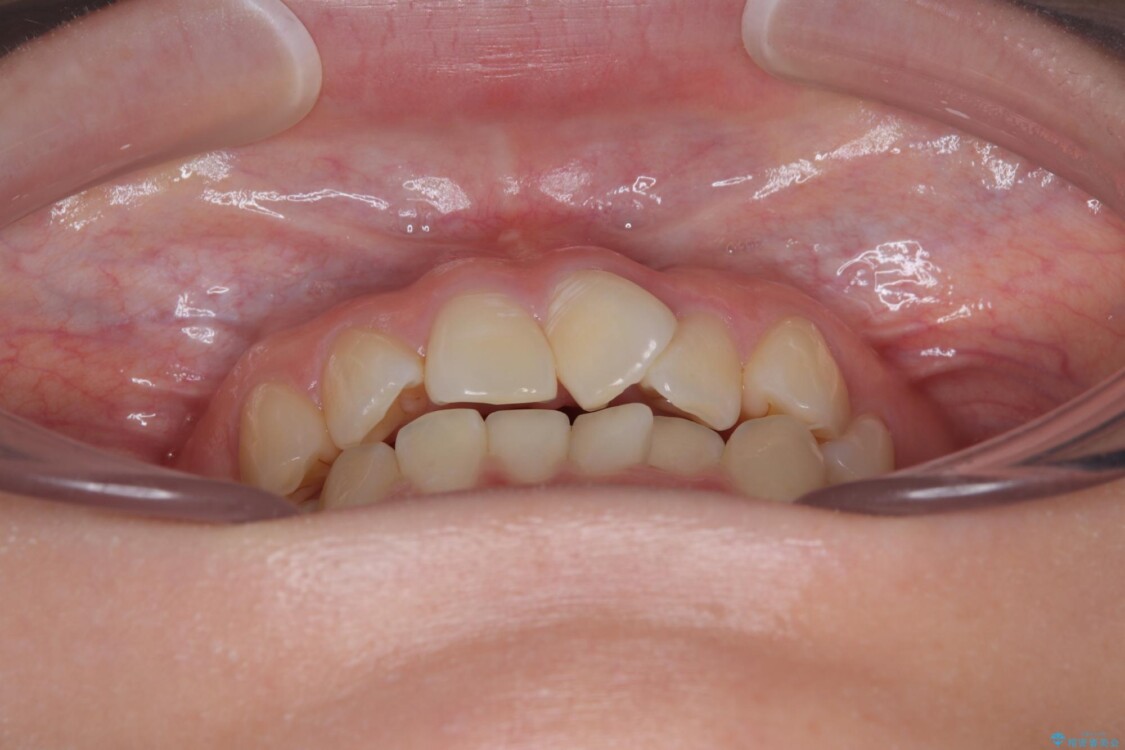

診察の結果、上下の前歯部に**叢生(そうせい/歯のガタガタ・重なり)**が認められました。

特に上の前歯にはねじれや重なりがあり、審美的にも清掃性にも影響している状態でした。

治療前

• 前歯のねじれ・ガタガタを10か月で改善!20代女性の矯正治療|クリアブラケットでむし歯になりにくい歯並びへ改善 治療前画像